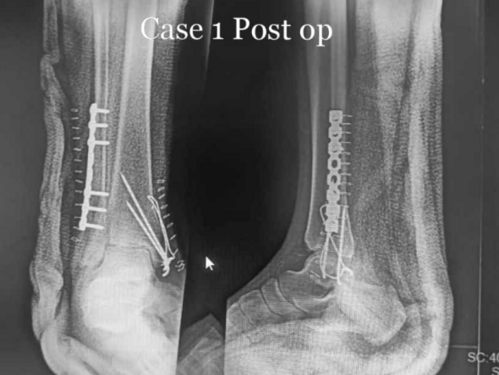

Managing a Bimalleolar Fracture: Surgical Intervention by Dr. Rahul Jagtap

Patient X, a 45-year-old male, encountered a distressing mishap while navigating down a staircase, leading to considerable anguish, swelling, and an i...